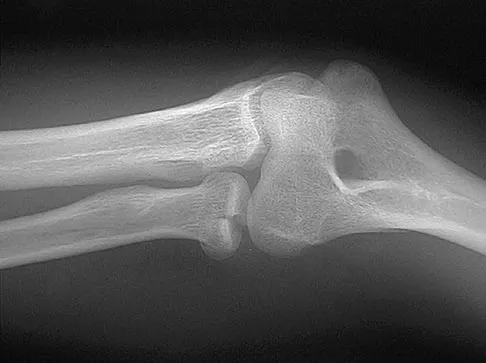

A 39-year-old woman fell onto her flexed elbow and sustained a comminuted displaced radial head and neck fracture. Radiographs confirm concentric reduction of the ulnohumeral joint. Examination reveals pain with compression of the radius and ulna at the wrist. What is the best treatment for the radial head fracture?

Explanation

Patients with comminuted radial neck and head fractures and associated wrist pain have a significant injury to the elbow and forearm. Nonsurgical management is an option, but initial casting will result in stiffness and early range of motion is likely to be unsuccessful secondary to pain. Surgical treatment with open reduction and internal fixation, although possible, is technically demanding and results are unpredictable with comminuted fractures. Excision alone in the face of wrist pain may lead to radial shortening. The treatment of choice is excision and metallic radial head arthroplasty. Silastic implants have been associated with synovitis and wear debris. Furry KL, Clinkscales CM: Comminuted fractures of the radial head: Arthroplasty versus internal fixation. Clin Orthop 1998;353:40-52.